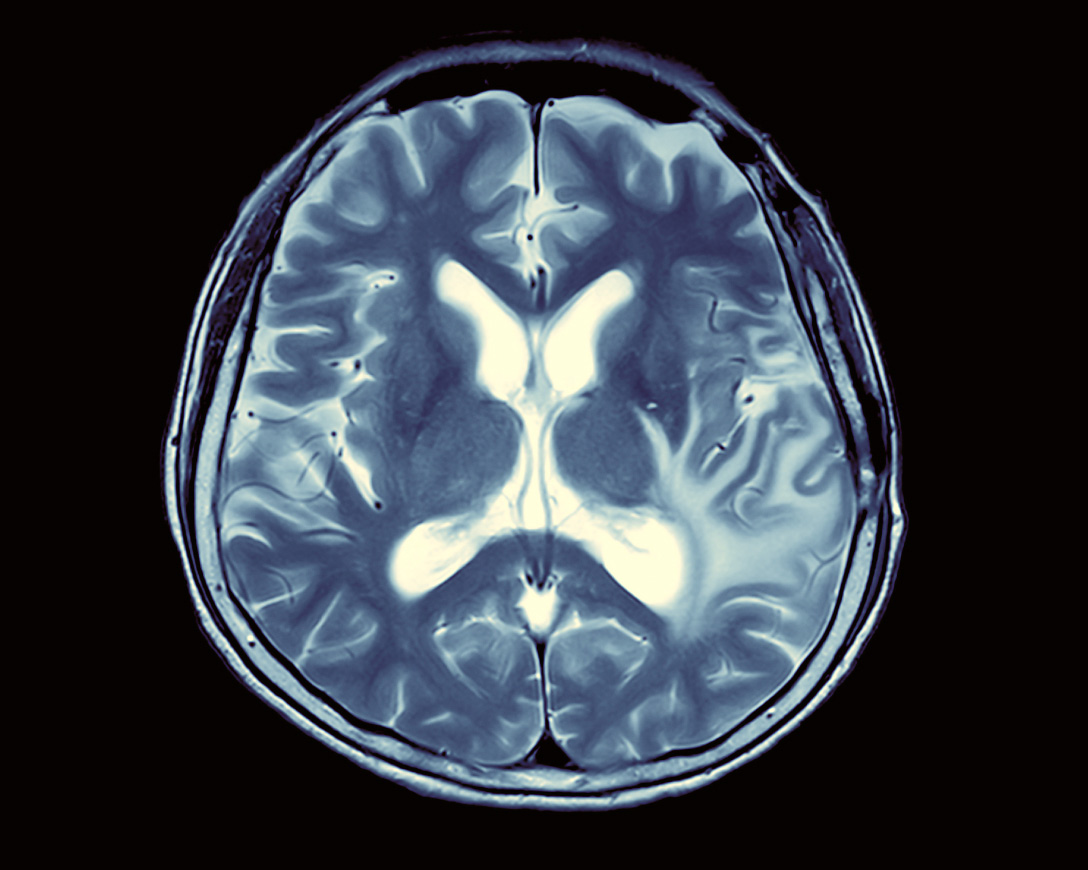

Ядерная медицина — одно из современных направлений диагностики и лечения с использованием радиоактивных изотопов. Лучи, испускаемые изотопом, дают возможность высвечивать те нарушения в работе органа, которые никаким другим способом обнаружить практически нельзя. С помощью такой диагностики можно выявить онкологические заболевания на ранних стадиях, а значит, дать возможность победить болезнь. Мировой рынок услуг ядерной медицины оценивается в 80 миллиардов долларов, а через шесть лет, по прогнозам, он вырастет до 300 миллиардов.

Ядерная медицина включает лучевую и радионуклидную терапию, нацеленную на уничтожение раковых клеток. Радиофармпрепараты обладают коротким и минимально вредным для человека периодом полураспада. С помощью новейших разработок в сфере радиохирургии, например киберножа, можно удалить труднодоступную опухоль и ее метастазы без хирургического вмешательства даже в головном мозге. У «Росатома» есть богатый опыт работы с радиоактивными изотопами, поэтому госкорпорация вовлечена в разработку радиофармпрепаратов, радиотерапевтических комплексов и ведет работы по созданию в России центров ядерной медицины.